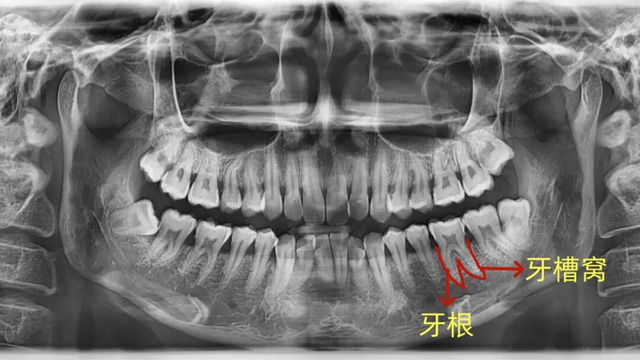

牙槽骨:牙齿的“土壤”

我们的牙根就像大树的根,深深扎根在牙槽骨里,每颗牙都有自己独立的“坑位”(牙槽窝),这是牙齿最核心的支撑。

牙周膜:牙齿的“减震器”

在牙根和牙槽骨之间,有一层充满弹性和韧性的薄膜,叫牙周膜。它既能固定牙根,又能缓冲我们咀嚼时的冲击力,保护牙齿和牙槽骨不受损伤。